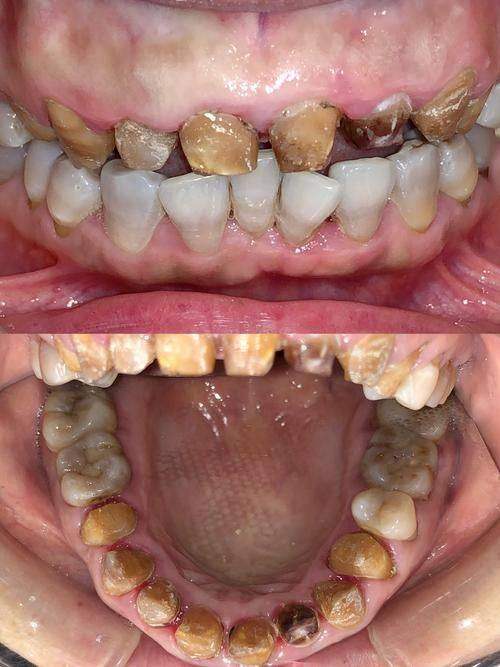

在我鲜艳的二十岁时,我做了一个令人难以置信的决定——我选择了烤瓷牙。整整17颗牙的烤瓷,让我经历了不同寻常的痛苦,甚至在日后的生活中带来了困扰。作为一名年轻人,我急于追求理想的笑容,却在无良医生的引导下,走向了深渊。与其说是为了美观,我更是付出了健康的代价。本文将围绕我二十岁烤瓷了17颗牙的经历展开深度剖析,向大家分享我的病痛历程及宝贵经验,以此来警示每一个渴望美牙的人们,如何选择更适合自己的护牙方式,避免不必要的牙齿健康危机。

在我的牙齿健康遭遇到危机之前,我从未想过烤瓷牙会给我带来如此巨大的麻烦。作为一个年轻女性,我从小就对牙齿不太满意,尤其是前牙的拥挤和不整齐。在无良医生的向导下,我被告知必须要做17颗烤瓷牙,总费用高达3万元。起初,我觉得为了一个美好的笑容值得这些。

然而,经过几年后,烤瓷牙的问题开始显露出来,导致我每一天都过得郁闷而焦虑。牙龈发炎、腐臭味和不时的隐痛侵扰着我的生活,而医生却告诉我这些都是由于烤瓷牙不当操作引起的。我不禁反思,烤瓷牙是否真的能够改善我的牙齿健康?

医生建议我拆掉这些烤瓷牙,开始进行更为基础的治疗。被欺骗的感觉让我愤怒,我恨那位不负职责的医生。在此之前,我甚至不知道自己的真牙已经遭到腐蚀,到了不得不拔掉的地步。